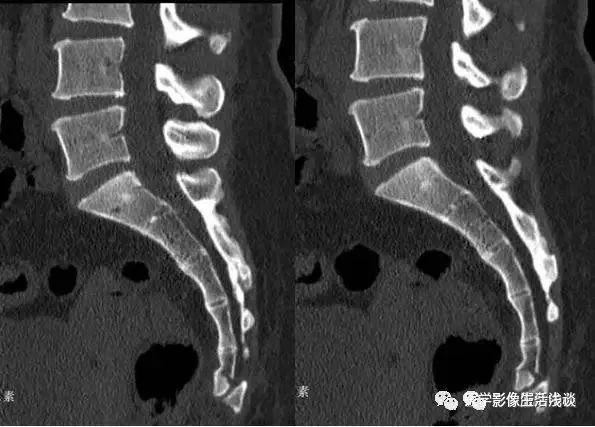

按不同的弯曲形态将其分为:均匀弯曲型、骶骨成角型、尾骨成角型、尾骨脱位型4种类型(见图1- 9),其中骶骨成角一般在S3、S4-5和S5部位,成角最大为70°。尾骨成角常在尾1-2或尾2-3部位,成角最大可达80°。

图1 均匀弯曲型;图2 骶骨成角型(骶3);图3 骶骨成角型(骶4-5);图4 骶骨成角型(骶5);图5尾骨成角型(尾1);图6 尾骨成角型(尾1-2);图7 尾骨成角型(尾2-3 );图8 尾骨脱位型;图9尾骨脱位型。

(2)尾骨成角,向前 倾斜,关节间隙尚好,无骨折片,易误认为尾骨脱位(见图5-7);